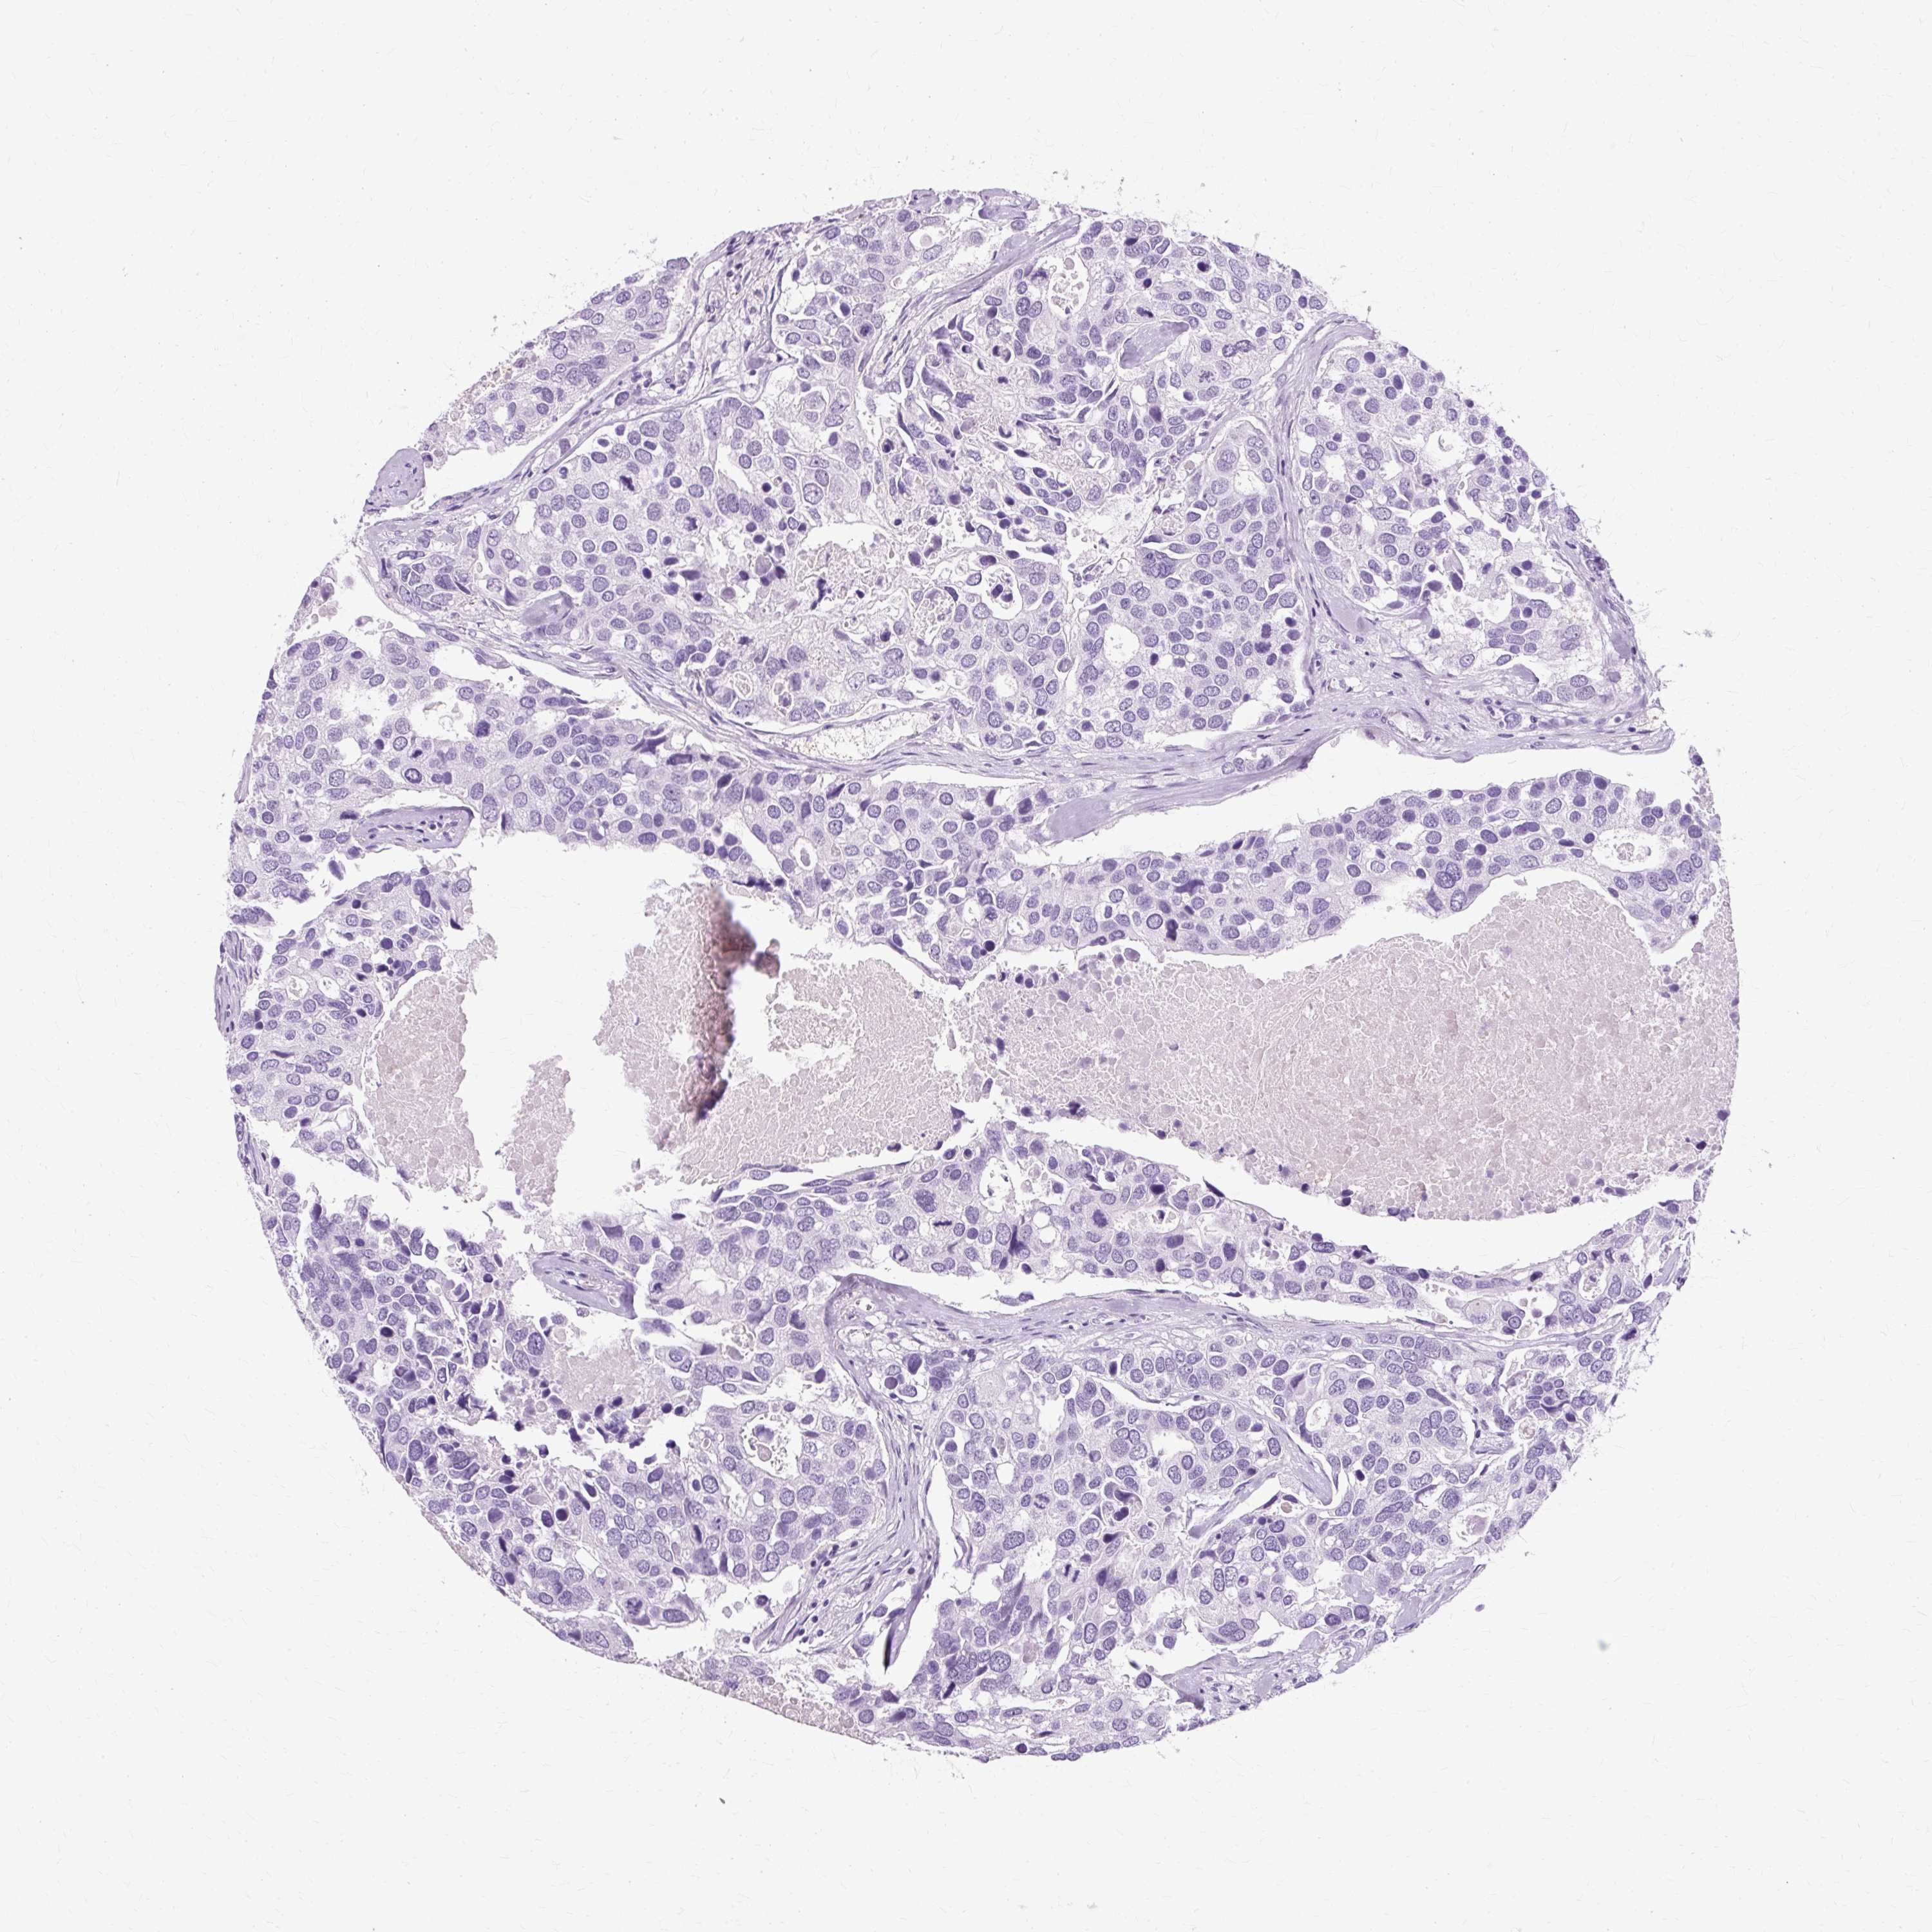

CANCER BREAST CANCER Show tissue menu

Breast cancer

Human cancer